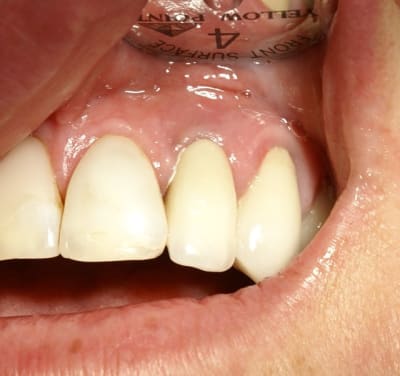

Tout à fait d'accord growler et c'est d'ailleurs ce que l'on peut voir sur le cas suivant. Fracture radiculaire, aucune infection periradicualire. Extraction et implantation immediate. Espace existant entre l'implant et l'alvéole est comblé par du BioOss. Un logement sous gingival est formé en vestibulaire et palatin de facon à pouvoir recouvrir le tout par BioGide et un conjonctif enfoui.

L'implant est de 15mm mais l'alvéole était large et 50% environ de la surface implantaire n'était en contact qu'avec du BioOss. J'ai pour cela préféré enfouir.

Situation semblable.

Jeune homme, 20 ans, accident de vélo.

Perte de 11 et 21.

Arrive dans mon cabinet 8 jours post trauma.

J'ai placer sous antibio et 2 jours après j'ai curetté les alvéoles, fait lambeau (perte de paroie buccale), placer 2 4,6 X 15 mm en palatin, greffe MINEROS, membranne (suturée sous le lambeau palatin + 2 tacs en titane au buccal).

Extension du lambeau au buccal et fermeture.

Ah oui, freinectomie laser en mêm temps, histoire de s'occuper un peu. Pas de temporisation sur implants avec une perte d'os au buccal. Prothèse acrylique amovible de transition, placée 7 jours post-op.

La 2e photo est 7 jours post-op, la sem dernière.

Zéro enflure, zéro douleur, pas d'anelgésique.